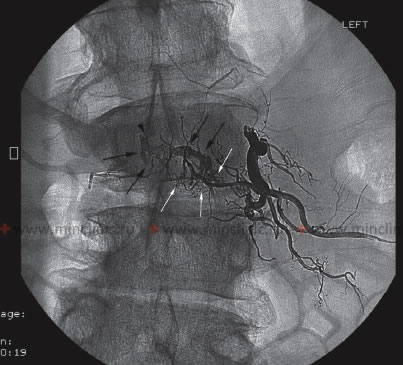

Хирургические процессы при эмболизации гемангиомы на фото

Раздел: Снимки-откровения